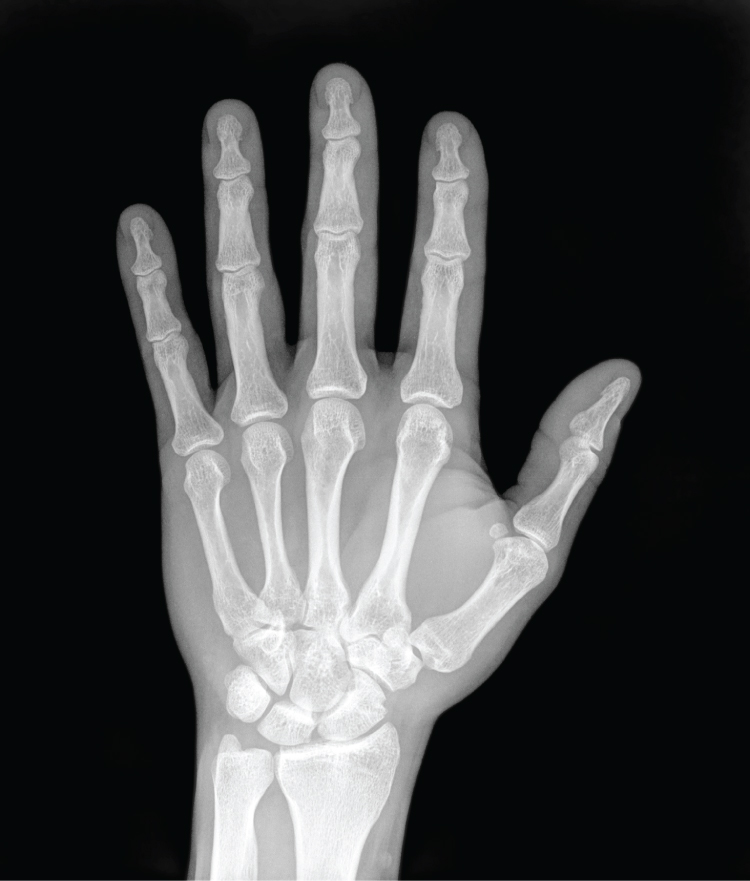

German physicist Wilhelm Röntgen (1845–1923) was experimenting with electrical current when he discovered that a mysterious and invisible “ray” would pass through his flesh but leave an outline of his bones on a screen coated with a metal compound. In 1895, Röntgen made the first durable record of the internal parts of a living human: an “X-ray” image (as it came to be called) of his wife’s hand. Scientists around the world quickly began their own experiments with X-rays, and by 1900, X-rays were widely used to detect a variety of injuries and diseases. In 1901, Röntgen was awarded the first Nobel Prize for physics for his work in this field.

The X-ray is a form of high energy electromagnetic radiation with a short wavelength capable of penetrating solids and ionizing gases. As they are used in medicine, X-rays are emitted from an X-ray machine and directed toward a specially treated metallic plate placed behind the patient’s body. The beam of radiation results in darkening of the X-ray plate. X-rays are slightly impeded by soft tissues, which show up as gray on the X-ray plate, whereas hard tissues, such as bone, largely block the rays, producing a light-toned “shadow.” Thus, X-rays are best used to visualize hard body structures such as teeth and bones (Figure 1.5.1). Like many forms of high energy radiation, however, X-rays are capable of damaging cells and initiating changes that can lead to cancer. This danger of excessive exposure to X-rays was not fully appreciated for many years after their widespread use.

Refinements and enhancements of X-ray techniques have continued throughout the twentieth and twenty-first centuries. Although often supplanted by more sophisticated imaging techniques, the X-ray remains a “workhorse” in medical imaging, especially for viewing fractures and for dentistry. The disadvantage of irradiation to the patient and the operator is now attenuated by proper shielding and by limiting exposure.